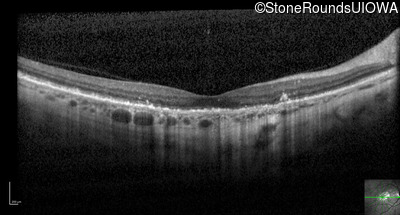

Optical Coherence Tomography - Right - 20/63

Exemplar / OCT Stack